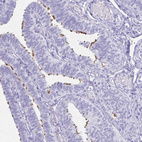

Immunohistochemical staining of human bronchus, fallopian tube, rectum and tonsil using Anti-CCDC39 antibody HPA035363 (A) shows similar protein distribution across tissues to independent antibody HPA035364 (B).